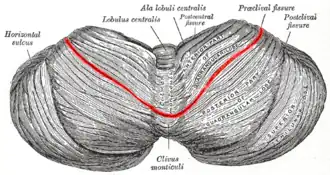

Upper surface of the cerebellum. (Preclival fissure coloured in red.) | |

The monticulus of the cerebellum is divided by the primary fissure (or preclival fissure) into an anterior, raised part, the culmen or summit, and a posterior sloped part, the clivus; the quadrangular lobule is similarly divided.